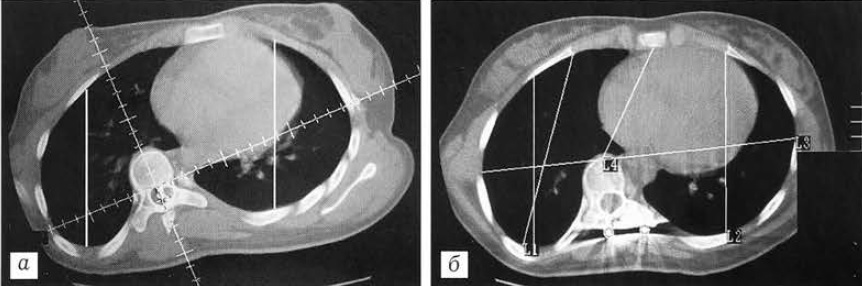

Рис. 1. Схема измерения ротации позвонка по методике Ааго и Dahlborn относительно передней срединной линии (а) и относительно сагиттальной плоскости (б).

Для объективизации результатов исследования и оценки степени изменений формы и размеров грудной клетки мы ввели и изучили 4 основных параметра (измерения проводили на уровне вершины деформации) (рис. 2): расстояние от внутренней поверхности грудины до передней поверхности тела позвонка (1); расстояние между наиболее удаленными точками боковых поверхностей грудной клетки в плоскости, максимально приближенной к фронтальной (2); расстояния от наиболее дорсальной точки грудной клетки справа и слева (вершина гиббуса) до наиболее вентральной точки с соответствующей стороны (3 и 4). При тяжелых деформациях мы дополнительно измеряли расстояния от боковой поверхности тела позвонка справа и слева до боковой поверхности грудной клетки с соответствующей стороны в сагиттальной плоскости (5).

Рис. 2. Основные параметры, используемые для определения размеров и формы грудной клетки у больных сколиозом (пояснения в тексте).

Очевидно, что улучшение формы грудной клетки, т.е. стремление к симметричной правильной овальной форме, будет сопровождаться следующими изменениями значений исследуемых параметров: уменьшением расстояния от внутренней поверхности грудины до передней поверхности тела позвонка (1); некоторым уменьшением расстояния между наиболее удаленными точками боковых поверхностей грудной клетки (2); увеличением на вогнутой стороне деформации и уменьшением на выпуклой стороне (стремление к уравниванию) расстояния от наиболее дорсальной до наиболее вентральной точки грудной клетки (параметры 3 и 4).